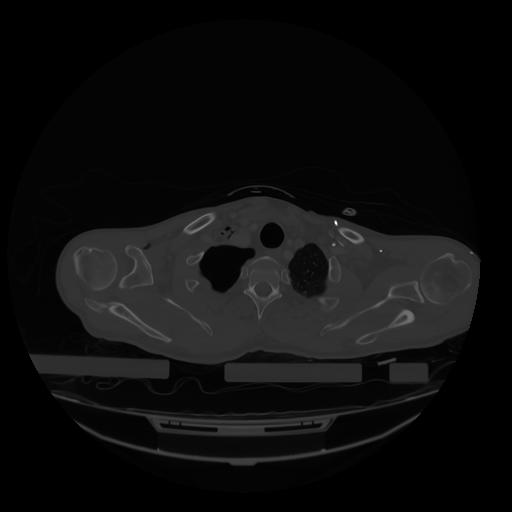

28 CUERPO,CE,Vol,2.0,CUERPO,,